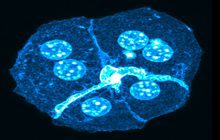

- Perform tunnel technique to evaluate apoptosis

On the other hand, in cutting-edge sciences such as tissue engineering, the use of up-to-date techniques for section preparation and cell tracking and engineered tissue structure has contributed significantly to the development of new studies.